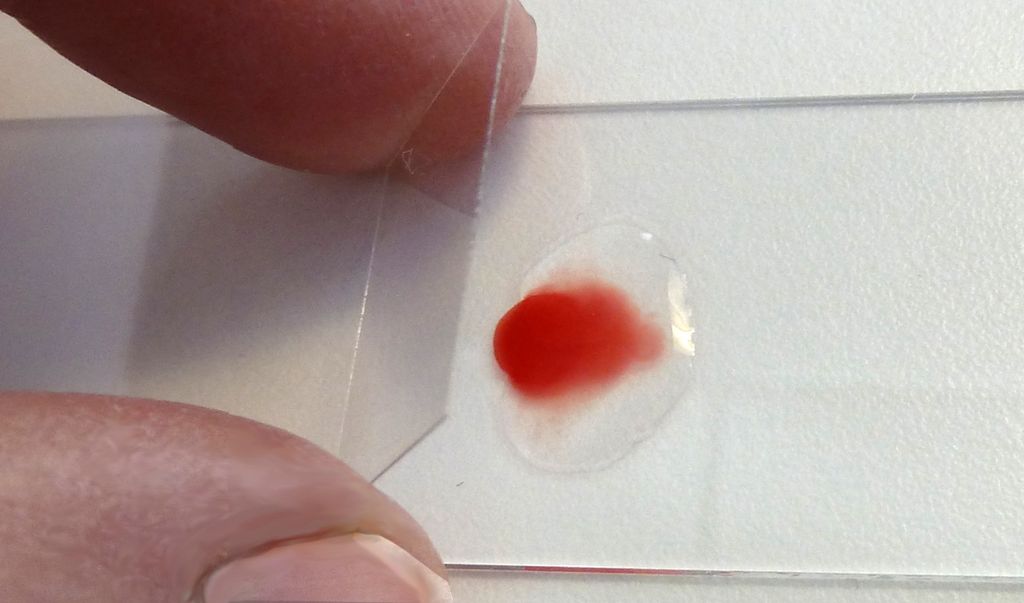

- Stikk et hull på siden av en finger, og klem ut en bloddråpe.

- Lag et mikroskopipreparat ved å plassere bloddråpen på et objektglass, og stryk den utover med et annet objektglass. Bloddråpen bør være så tynn som mulig. Legg over dekkglass.